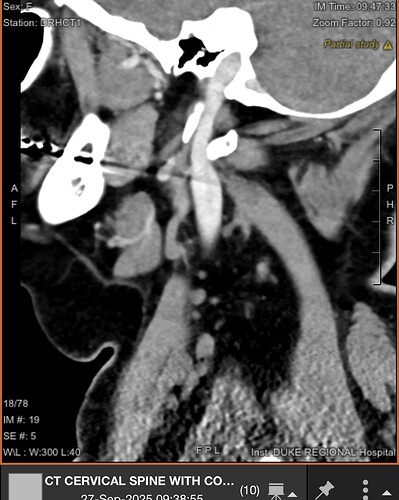

Ok...here's my CT...and no mention of styloids, but I think they are compressing IJV..Opinions?

brain fog, headache, ear fullness, conductive hearing loss, ear pain, dysphagia, gastroparesis, pulsatile tinnitus, tinnitus, balance problems, eye watering, double vision, ptosis of my eye, trouble with visual tracking, and exercise intolerance. I also have confirmed IIH. Of course, the radiologist did not comment on the CT Scans, so here I am asking for an opinion. I think I see jugular compression here between C1 and the styloid. I don’t have the CD, but I can get it.

@Nanc765 Good job posting helpful images! It sure looks like you have bilateral IJV compression. You have one very interestingly shaped styloid & on the other side it appears that you have a chunk of calcified stylohyoid ligament but not an elongated styloid, however, that image may have been taken further from the skull base than the other one so your styloid may be helping w/ the compression on both sides. Your symptoms do align with those seen w/ IJV compression.

I agree with the others. I think you’d benefit from bilateral styloidectomy above the level of C1 to open the IJVs up